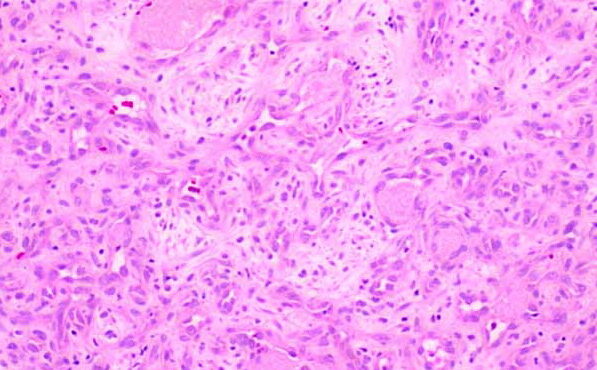

Graft versus Host Disease =داء رفض الطعم للمضيف Graft Versus Host Disease GVHD occurs in situations in which donor immunocompetent T cells transferred into allogenic hosts are incapable of rejecting them. The sources of the T cells include primarily peripheral blood stem cell and bone marrow transplants and, infrequently, unirradiated blood products , solid organ […]